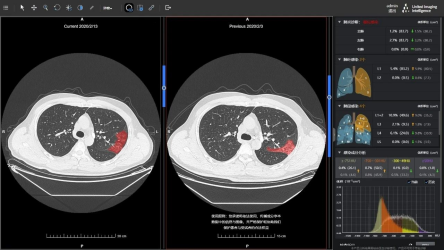

uAI新冠肺炎医学影像智能化诊断全栈解决方案

该方案基于人工智能技术,从成像、筛查、诊断到随访,以AI全栈助力抗“疫”。uAI新冠肺炎智能辅助分析系统通过高敏感度检测与分类算法,提升病灶检出率,辅助筛查疑似病患,对新冠病毒感染病灶勾画重合率超过90%,全肺感染百分比量化误差小于1%,可将5至10分钟的CT阅片时间缩短至1分钟以内。

uAI新冠肺炎智能分析系统随访评估功能